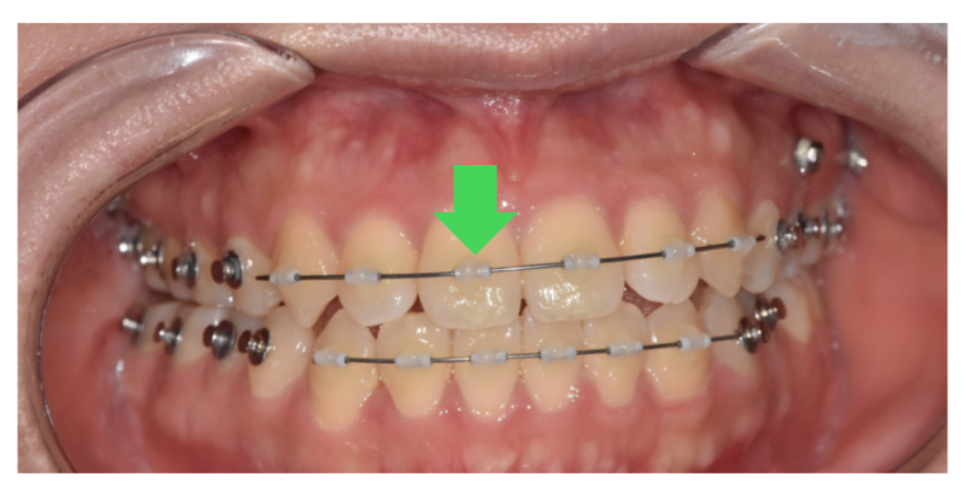

Mini Tube Appliance라고 하여

아주 작은 튜브 형태의 브라켓을 치아 표면에 부착하여

와이어를 연결하는 방식입니다.

작고 얇으며

치아 색깔과 비슷하여 티가 많이 나지 않습니다.

MTA 장치는 말 그대로 여러 개의 튜브(관형 브라켓)를 활용하여

앞니에 정확한 방향과 강도의 힘을 가할 수 있는 교정 시스템입니다.